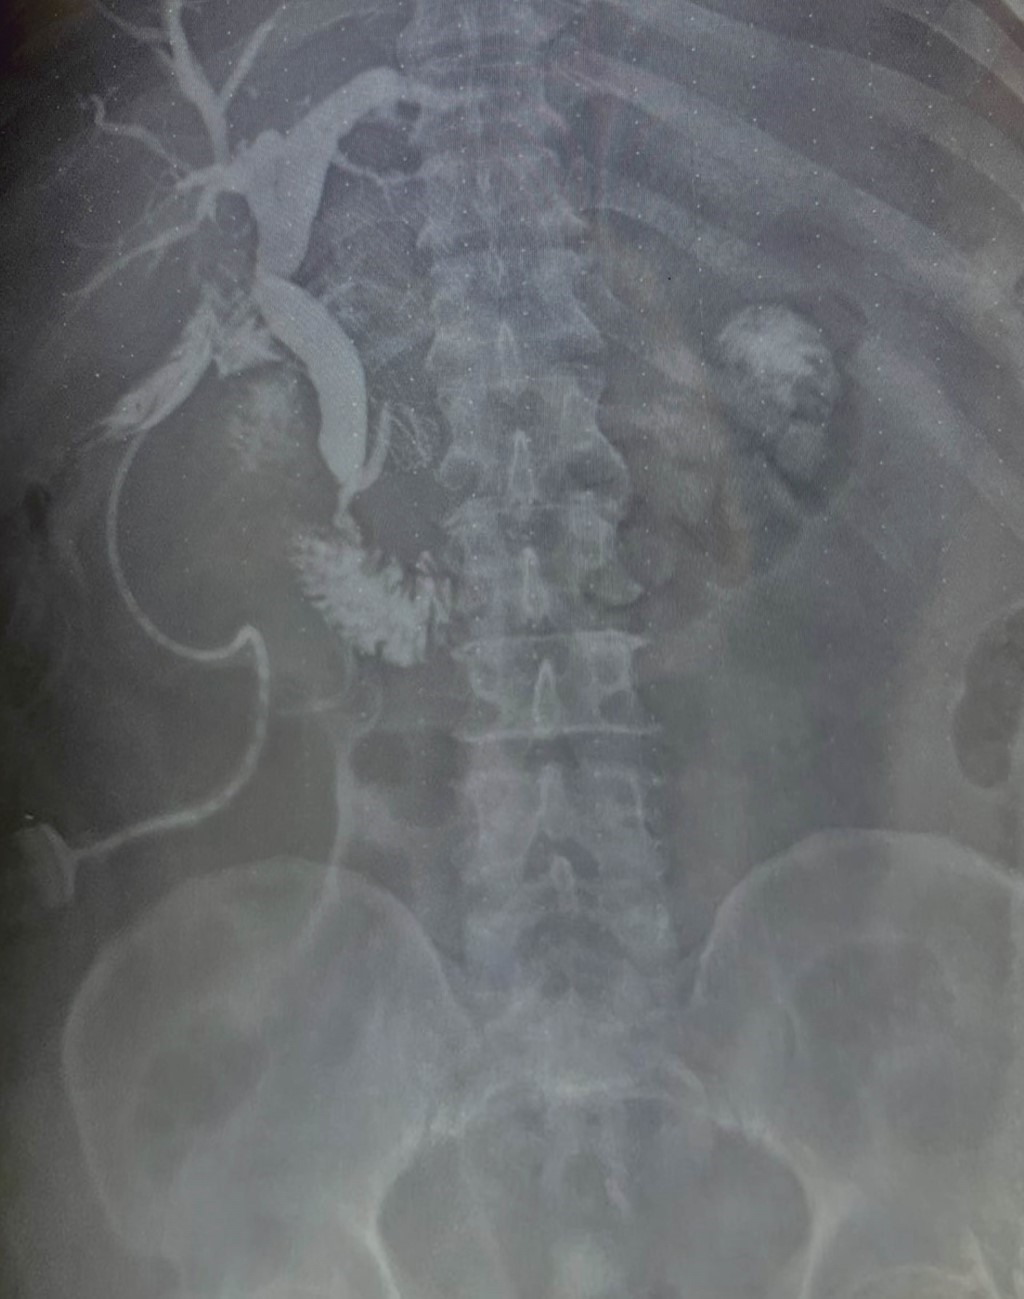

Masculino de 64 años, quien inicia su padecimiento con ictericia, negando otra sintomatología, llama la atención que se manifesta durante al menos tres días previos a su llegada a urgencias, su exploración física sin alteraciones, los laboratorios revelan una bilirrubina total de 25 mg/dl, bilirrubina directa de 22 mg/dl, fosfatasa alcalina 235 UI/l, gamma-glutamil transferasa 157 UI/l, creatinina 2.5 mg/dl, el resto de los laboratorios normales, se le realiza un ultrasonido de abdomen que reporta vesícula biliar mal definida, y dilatación de la vía biliar de 19 mm (Figura 1), se observa lito en colédoco de alrededor de 12 mm. Se integra el diagnóstico de coledocolitiasis, no obstante, se solicitan marcadores tumorales, con reporte de CA 19-9 de +8,000 UI; se solicita colangiorresonancia, la cual evidencia dilatación de vía biliar (vb) de 20 mm, lito de 16 mm a nivel del ámpula, no se reporta morfología de la vesícula biliar (VB), paciente candidato a colangiopancreatografía retrógrada endoscópica (CPRE) según el servicio de Gastroenterología. Se le realiza CPRE sin poder extraer lito, se programa para colecistectomía con exploración de vía biliar, el transoperatorio revela biliperitoneo, lisis de VB, fístula colecistocoledociana (Figura 2), litio único de 15 mm, se coloca sonda T, no se cuenta con servicio de cirugía hepatopancreatobiliar, por lo que no se realiza reparación definitiva, colangiografía transoperatoria revela paso de material de contraste a duodeno, sin fugas aparentes por orificio fistuloso (Figura 3), evolución posoperatoria favorable, el drenaje por sonda T en promedio 500 ml por día con disminución progresiva, con mejoría de hiperazoemia, con flujo urinario mayor a 0.5 ml/kg/h, colangiografía posoperatoria sin fugas, paso de medio de contraste a duodeno, reporte de patología revela adenocarcinoma de vesícula moderadamente diferenciado con infiltración a muscular (Figura 4). El paciente rechaza tratamiento médico y decide egreso voluntario, comprende y acepta los riesgos, no contamos con seguimiento a largo plazo.

Figura 2